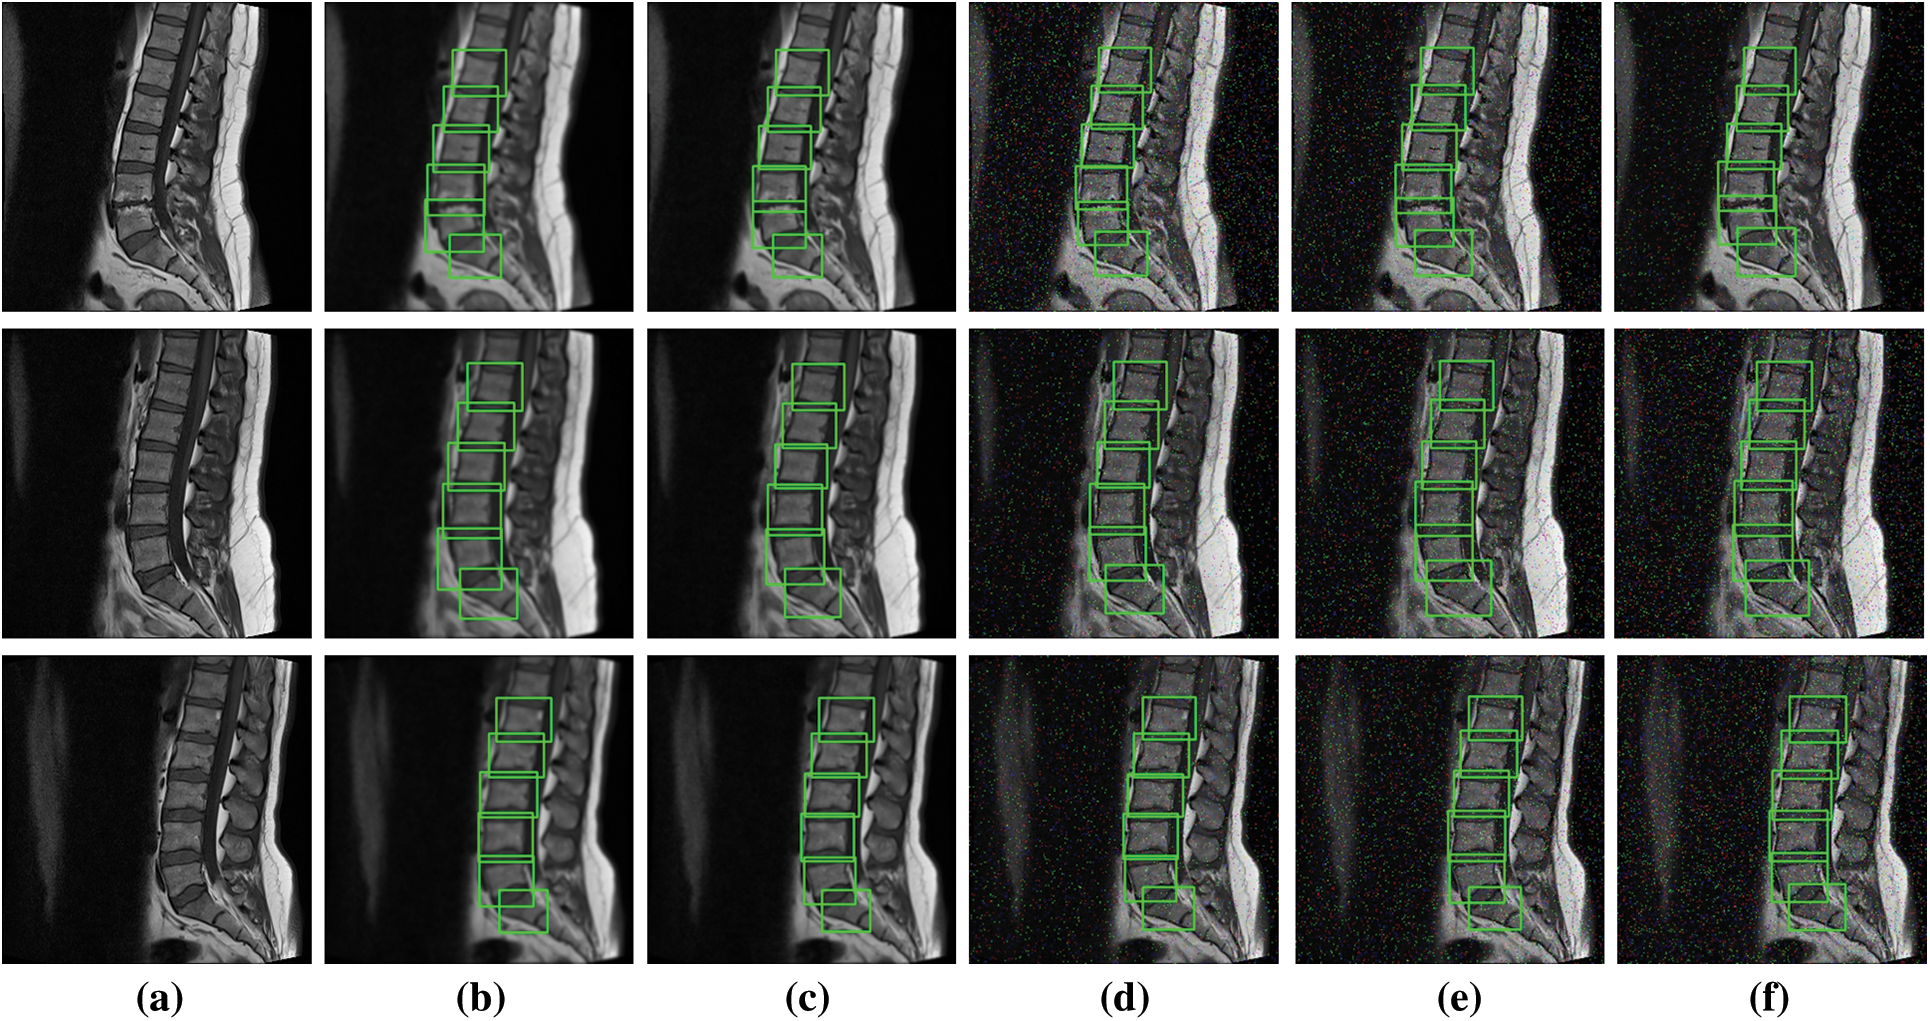

To further elaborate the robustness of our proposed framework, noise based results of YOLOv5s are illustrated in Fig. 6. We have added Gaussian and Salt & Pepper noise for the experimentations. The results clearly shows an outstanding performance of YOLO architecture.

Figure 6: Noise based localization results (a) Original image, (b) and (c) Gaussian noise with sigma 1.5 and 1 (d), (e) and (f) Salt and pepper noise with densities 0.02, 0.03 & 0.05